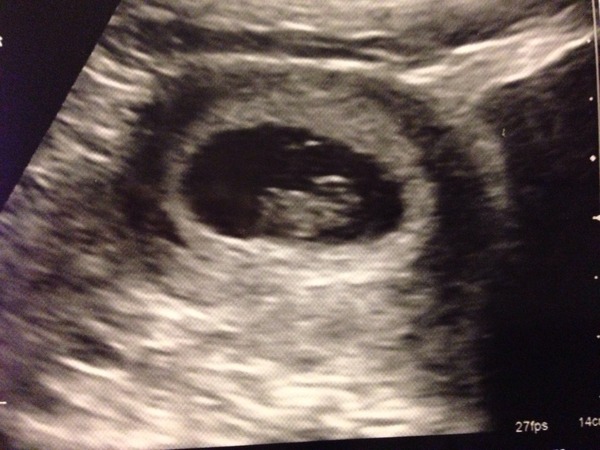

Little tea checking in. Everything looked good in the scan, heart thundering away and dated at 8+2 which is exactly what I thought so fingers crossed it all keeps going as well. Feels very real now!

September 2015 (#3) bring on the scans as our waists expand!

Love the scan pics Hare and Tea, very sweet little squishes! :)